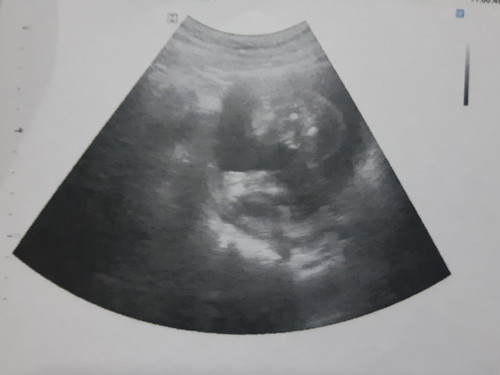

ลูกได้19wนอนคว่ำ ซาวด์เพศไม่ชัด

ลูกนอนคว่ำ ซาวด์เพศไม่ชัด ใครดูเป็นบางค่ะ

รูปไม่ชัดเลยจ้า